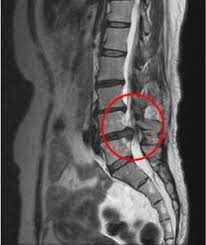

次に背骨や腰の痛みの原因を調べる検査です。椎間板ヘルニアや神経の圧迫を画像で確認することができます。

脊椎・腰椎(ヘルニアなど)